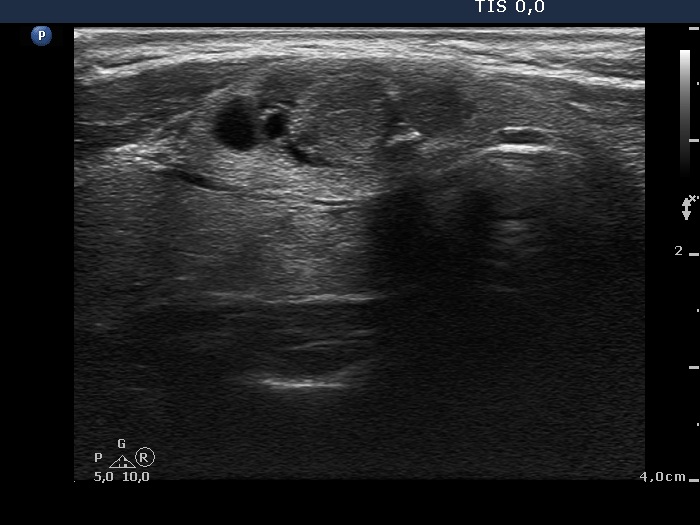

First examination (first row of images):

Clinical presentation: A 31-year-old woman was referred for evaluation of a nodule discovered by herself.

Palpation: a not firm nodule in the isthmus.

Hormonal evaluation: euthyroidism with TSH 0.75 mIU/L.

Ultrasonography. The thyroid was echonormal. There was a small, moderately hypoechogenic lesion in the lower part of the left lobe while a larger nodular area was located in the isthmus. The latter was composed of hypoechogenic and echonormal parts and presented cystic degeneration, as well.

Aspiration cytology of the isthmic nodule disclosed a follicular lesion with signs of hyperthyroidism.

We indicated scintigraphy which revealed an autonomously functioning nodule according to the lesion in the isthmus. We suggested follow-up, yearly TSH determination.